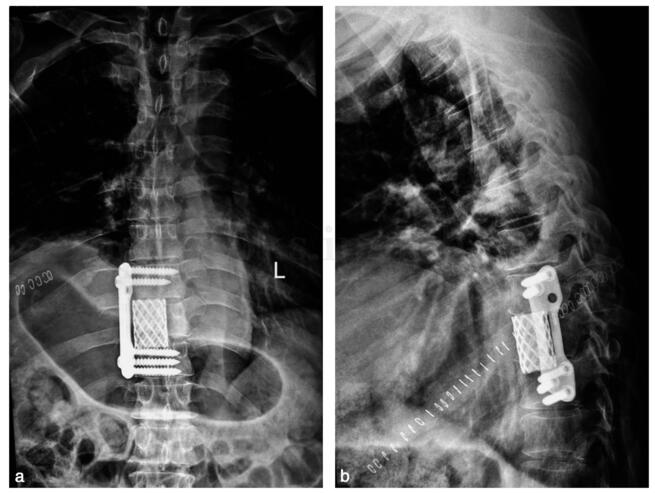

手术治疗:在全麻下行“前路开胸右第7 肋切除,第9 胸椎肿瘤切除椎管减压,Mesh +骨水泥填充植入钛板内固定术”。术后X 线片见图21‐3。

图21‐3 术后X 线片